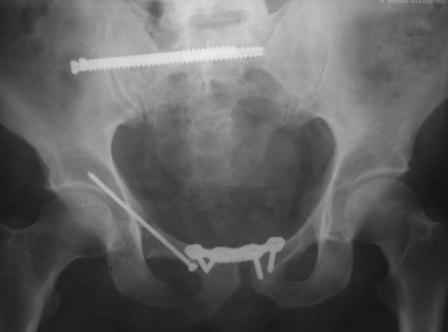

Уважаемые коллеги! Мы хотели узнать Ваши мнения или есть у кого либо опыт по закрытому остеосинтезу лонной кости винтом. Дело в том, что нами недавно впервые в нашей клинике проведен закрытый остеосинтез лонной кости канюлированным винтом. Пациент поступил с д-зом: Политравма(PTS-42 балла). закрытый 6-В2 перелом таза. тупая травма живота. Разрыв селезенки. ЗЧМТ.УГМ.При поступлении шинирование таза передней рамой, в противошоковом зале проведен КТ, где выявлен перелом лонной и седалищной кости со смещ. КПС целый, боковая масса крестца без смещения (компрессионный), damage control, спленэктомия. На 5 сутки с момента поступления проведена вышеописанная операция, длительность операции 25 мин, разрез 3 мм под шляпку винта, на ЭОП-е и x-ray "вход и выход таза" винт расположен в лонной кости внутрикостно. Теперь сам вопрос: когда вертикализировать, есть ли у кого нибудь наблюдения по осложнениям (пациент на 2 сутки послеоперации встал и пошел без никаих проблем (наркоз СМА, подутро прижало по мальенкому). Помню, где-то видел подобные снимки, никак не могу найти (по моему у А.Ф. Лазарева). К сожалению, по техническим причинам никак не могу загрузить фото, уже 2 час пытаюсь не получается. Скрывать не буду, операция предоставило огромное удовольствие, технически не трудно выполнить, чем пластину ставить. Даже появилась идея предложить блокированный штифт для лона. Ерсин Жунусов.

в архиве нашел подобный случай

С Уважением А.Миронов(Новокузнецк)

Уважаемый коллега! Огромное спасибо за рекомендации и иллюстрации! Задний комплекс, а точнее КПС не стал фиксировать т.к. само сочленение и суставная поверхность крестца целое, на кт-срезе имеет место краевой перелом и то не завершенный, учитывая что передняя связка КПС целая (а она сами знаете мошная)не стали фиксировать и клинический пациент не регировал, только КТ. Еще на Ваших фото винты вошли через кортикальный слой или ближе к перелому, а у нас вход в лон получилось прямо с мыса симфиза, т.е. перелом слева, винт зашел справа налево. Или это не принципиально?. С уважением Ерсин Жунусов.

Уважаемые коллеги! спасбио Вам за советы и наставления! Рукводство получил, шикарно, отдельно спасбио А.Н.! Пациента сегодня активизировали, спокойно ходить с полной опорной нагрузкой. С уважением Ерсин Жунусов.

доступ.jpg

73KB (75258 bytes)